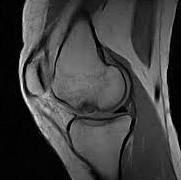

Gezien het hier om relatief grote defecten met dikwijls aantasting van het onderliggende bot gaat (breuk, osteochondritis dissecans) kunnen deze letsels opgepikt worden op een klassiek Rx. Voor verder detail is bij deze aanhoudende klachten (zwelling) altijd een MRI (scanner) noodzakelijk. Dit laat ons toe om de betrokkenheid (vasculaire status) van het omliggende bot correct in te schatten.